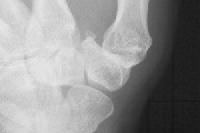

- Απλές ακτινογραφίες

- Σε προχωρημένο στάδιο, δυναμικές ακτινογραφίες.

Figure 1 BEFORE SURGERY